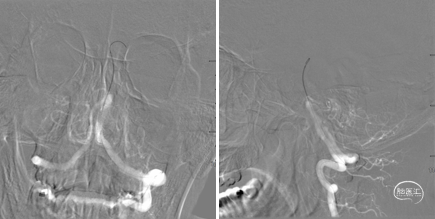

术前CT,ASPECT 8分。

术前CTA检查。

术前造影,BA近端闭塞。

术前造影,LC7次全闭塞。

术前造影,RICA 通过交通动脉向左侧颈内动脉及基底动脉尖代偿供血。